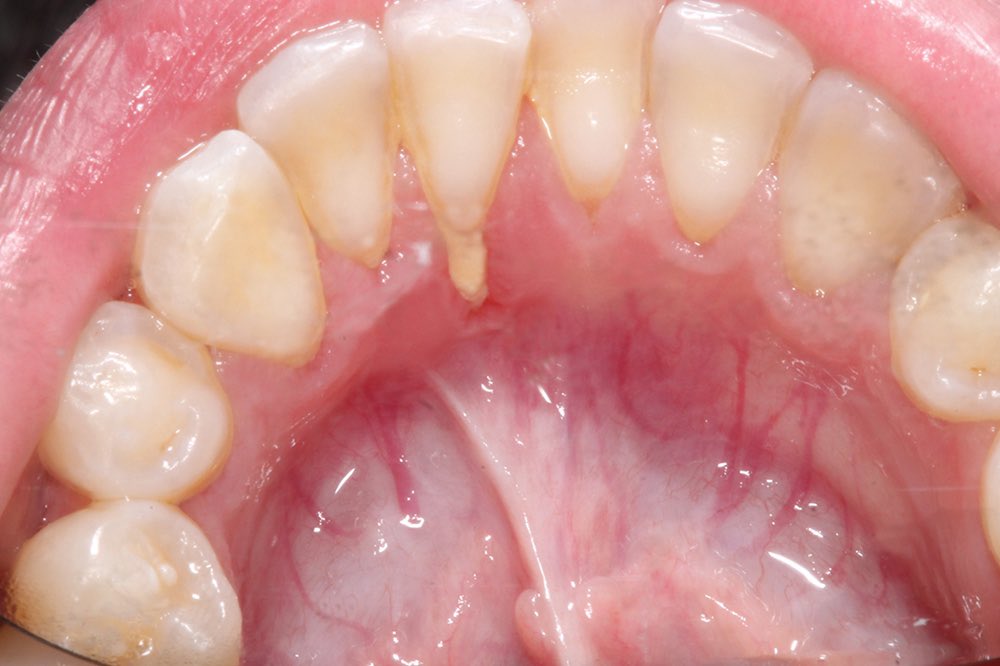

مع انتشار استعمال الحلق في منطقة الشفة واللسان.. أجد من واجبي التحذير من مضارها على المدى البعيد كإنحسار اللثة1️⃣أو تفرق الأسنان4️⃣والمدى القريب كالإلتهابات الحادة2️⃣وكسور الأسنان 3️⃣

فوجود هذه الاجسام المؤذية في مناطق دقيقة وحساسة غير مستحب